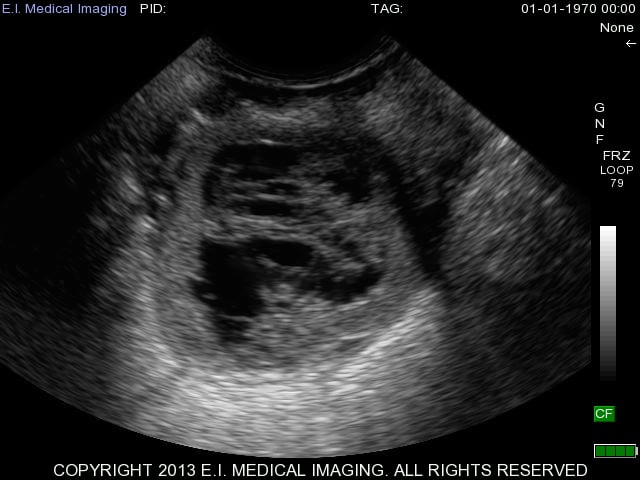

With luteal cysts originating from follicular cysts, the same mechanisms for follicular cysts development described above exist for luteal cysts. The major distinguishing factor between the two is that luteal cysts partially luteinize. Luteal cysts can also have different appearances on the ultrasound depending on the rate of luteinization. This is apparent in the next two images below depicting more examples of luteal cysts. You can see in this first image that luteinization has occurred along the bottom rim of the cyst and again the cobwebs of fibrous tissue are attempting to luteinize the rest of the cyst, but the upper portion of the lumen is still fluid-filled.

This second image is a luteal cyst (on the right side of ovary) in its early stages where the thin outer walls of the cyst still resemble that of a follicular cyst, but the cobwebs are apparent throughout the lumen as the cyst attempts to luteinize. You can see a second cyst on the left side of the ovary as well.